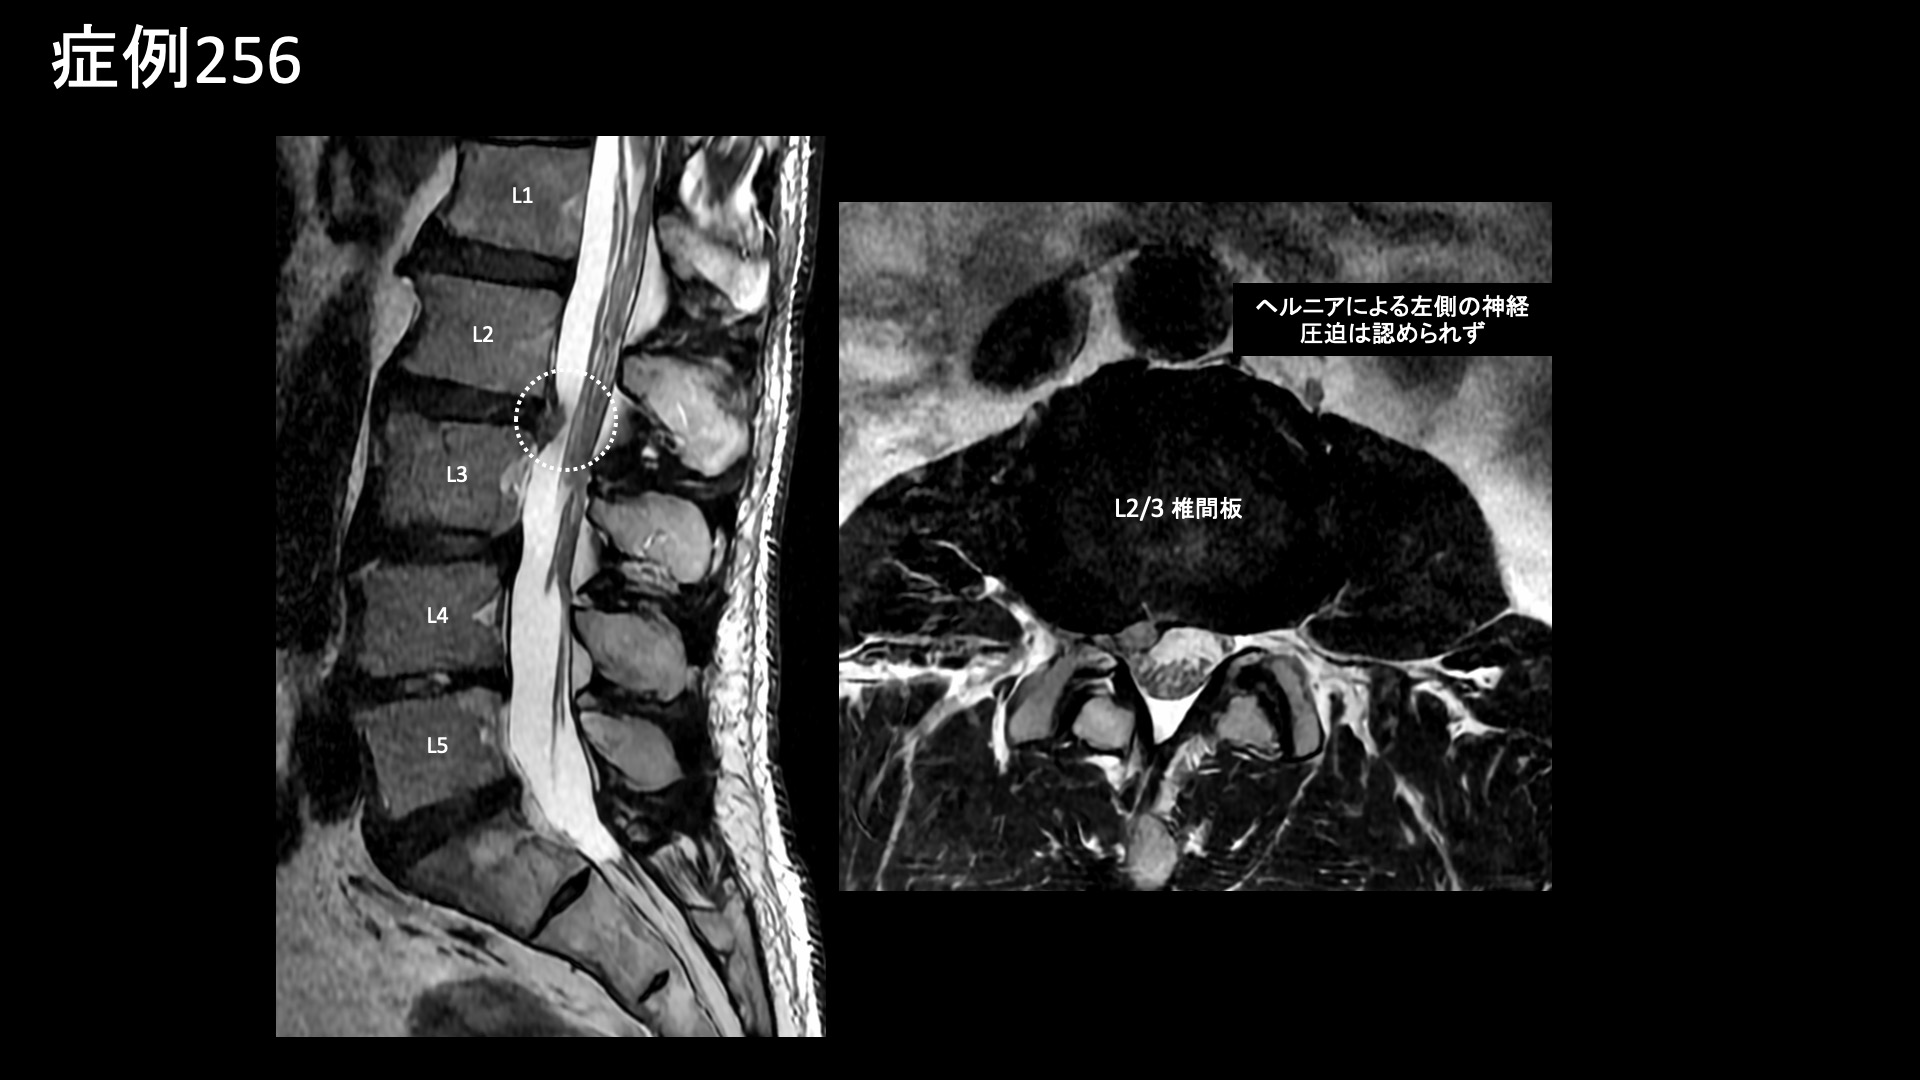

腰:椎間関節炎など 【60代:男性】15年前からの慢性腰痛が急激に悪化して夜も寝られず・・ヘルニアは悪さをしていないなら原因は?(筋・筋膜性疼痛症候群、仙腸関節障害、腰椎椎間板ヘルニア) 2025.12.23 鴨井院長による動画解説 受診までの経過 15年前から慢性的に腰痛がありました。1年前にひどい痛みと脱力に襲われ、MRI検査を受けたところ、腰椎椎間板ヘルニアと診断されました。手術も検討していましたが、自然軽快し、再び歩けるようになりました。しかしながら、右側の腰痛は軽快したものの、左側の強い腰痛が残っていました。ヘルニアで強く圧迫されていたのは右側の神経であったため、整形外科では首を傾げられました。じっとしていると増悪し、長時間の立位でも増悪しました。そのため、夜痛みで寝られないことが多く、起床後も11時くらいになってようやく動けるようになる状態でした。 *50年前に腸骨骨折の既往あり 診察時の所見 MRI検査を確認すると、やはりヘルニアで圧迫を受けているのは右側であり、ヘルニア所見と症状は合致しませんでした。腰の可動域をチェックすると。すべてに動作において中等度の制限がありました。股関節の内外旋動作では可動域は保たれているものの、動きに抵抗があり比較的高度の硬さがありました。触診では、第2―4腰椎レベルでは左腰部の筋肉部において有意に圧痛が認められました。レントゲンでは、左上前腸骨棘を中心に腸骨に骨表層不整像や骨硬化像が見られており、同部位に付着する腸骨筋、縫工筋、大腿筋膜張筋が関与する筋・筋膜性の障害が示唆されました。いずれも股関節の動きに関与する筋肉です。腸骨にはほかに腸腰筋や臀筋が関与し、いずれも腰臀部痛の原因として重要です。こうした腸骨の変化や、筋硬直、その他の特徴的な身体所見から総合的に判断して、筋・筋膜性疼痛症候群を主体として、仙腸関節障害も合併している状態と判断しました。骨盤の不安定性が一因ですので、腸骨骨折の既往とも関係があるかもしれません。以上より治療適応と判断し、モヤモヤ血管(病的新生血管)に対する運動器カテーテル治療(微細動脈塞栓術)を受けていただきました。 治療の所見 第2腰動脈~第4腰動脈の筋肉枝を選択的に治療し、さらに、腰痛の主要責任血管の一つである腸腰動脈や外側仙骨動脈、臀筋群に関与する上殿動脈、下殿動脈、股関節の動きにも関わる閉鎖動脈やその他の筋肉枝など複数個所の治療を広範囲に行いました。 治療後の経過 治療後2週間、まだ大きな変化はないものの、痛みが少しましになったほか、寝られる日が多くなってきました(以前は痛みで寝られないことが多かった)。治療後1ヶ月半、時々痛むことはあるものの、だいぶ良くなってきました。痛みで寝られないということは無くなりました。『本当に寝られなくて辛かったので嬉しい、何十歳か若返ったように思う』と大変喜ばれました。まだ左腰部に1か所だけ、塊のように感じる部分が残っているものの、それもだいぶ柔らかくなりました。治療後3ヶ月、塊の部分はやはり一定の違和感があるものの、痛みは感じなくなりました。全体的には疲れると疼くように痛むことがあるものの、元の7割程度の痛みは解消されました(3/10程度に改善)。夜寝られないほどの腰痛というのはかなり重症度が高いわけですが、これほどの状態であっても、MRIで原因がわからないことは珍しくありません。丹念に診察をして原因を見つけ出し、治療を行うのが痛み治療専門医師の腕の見せ所ですが、良い結果が得られて本当に良かったです。残存症状については追加カテーテル治療が有効ですが、生活習慣の改善や運動療法を地道に行っていくことでさらなる緩和が期待できます。引き続きしっかりとサポートしていきたいと思います。 本症例では、とにかく体の硬さや筋硬直が根底にありました。こうした状態では、腰痛はほぼ必発です。骨格のほか、運動不足や、過剰なトレーニング、急激な体重変動、加齢などが原因です。懸念のある方は、発症予防、再発予防のために硬さの解消に取り組んでください。原因により対処方法は異なりますが、日常的に軽めの運動を取り入れることはいずれの場合も有効です。 筋・筋膜性疼痛症候群の詳細はこちら 【70代:男性】頭痛、こめかみ・眉上の痛み、耳鳴り~頭部顔面の帯状疱疹後遺症に対するモヤモヤ血管治療(帯状疱疹後遺症) 前の記事 【50代:女性】8年前からの両膝・両足首の痛みに加えて踵まで痛み平地歩行もままならず・・進行性の変形性膝関節症および足関節症、足底筋膜炎の合併例に対して2回の運動器カテーテル治療を行った症例(変形性膝関節症、変形性足関節症、足底筋膜炎、肥満) 次の記事